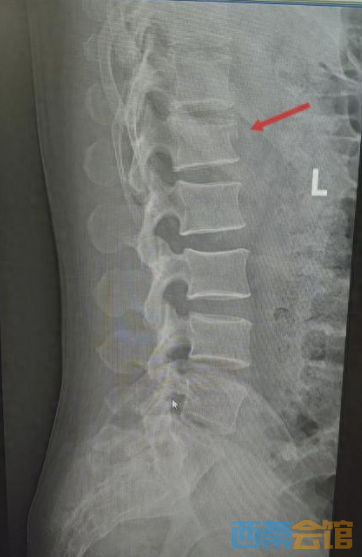

湖北日报讯(记者汪菁华、通讯员林国山)近日,45岁的周先生(化姓)从约3米高处意外坠落,臀部首先着地,当即感到腰骶部剧烈疼痛。情况紧急,他随即被送往武汉大学泰康临床学院/泰康同济(武汉)医院创伤外科,诊断为腰1椎体压缩性骨折。

患者伤情影像

3月12日,手术按计划进行。术中,在C臂机透视引导下,主刀医生张俊主任于患者腰背部选取1.5至2厘米的微小切口,经导针准确定位椎弓根,依次置入螺钉及连接棒,并对压缩椎体进行撑开复位。术中X线检查显示,骨折复位满意,内固定物位置良好。整场手术历时近3小时,过程顺利。